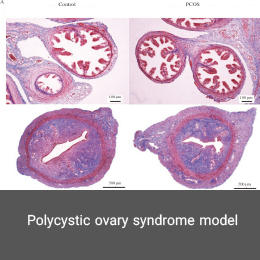

- Create and induce a variety of animal models